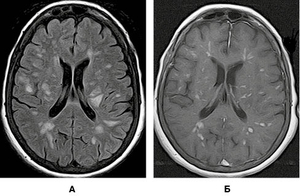

Завдяки виконаному МРТ-дослідженню головного мозку візуалізувано множинні вогнища, переважно овоїдної та округлої форм, розташовані в глибокій білій речовині обох семіовальних центрів. Вогнища гіперінтенсивні в режимах Т2/Flair і Т2, поліморфні. Типовою клінічною ознакою, характерною для перебігу ГРЕМ, на відміну від РС, є те, що більшість запальних вогнищ накопичують контраст. На зображеннях у режимі Т2 GRE не виявлено даних, які б могли свідчити про крововиливи в структурі вогнищ. МРТ-зображення головного мозку пацієнта в різних режимах, представлені на рисунках 6-9, підтверджують діагноз ГРЕМ.

Підписатися/images/nn257-1622023r6_.jpg)

/images/nn257-1622023r7_.jpg)

/images/nn257-1622023r8_.jpg)

/images/nn257-1622023r9_.jpg)